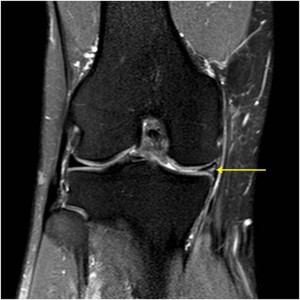

Le diagnostic commence par un examen clinique par votre chirurgien, qui recherche les signes caractéristiques d’une lésion méniscale. Cependant, l’examen de référence pour confirmer le diagnostic est l’IRM (Imagerie par Résonance Magnifique). Elle permet de voir précisément le type, la taille et la localisation de la lésion, et de vérifier l’état du cartilage et des ligaments.

IRM : Lésion méniscale